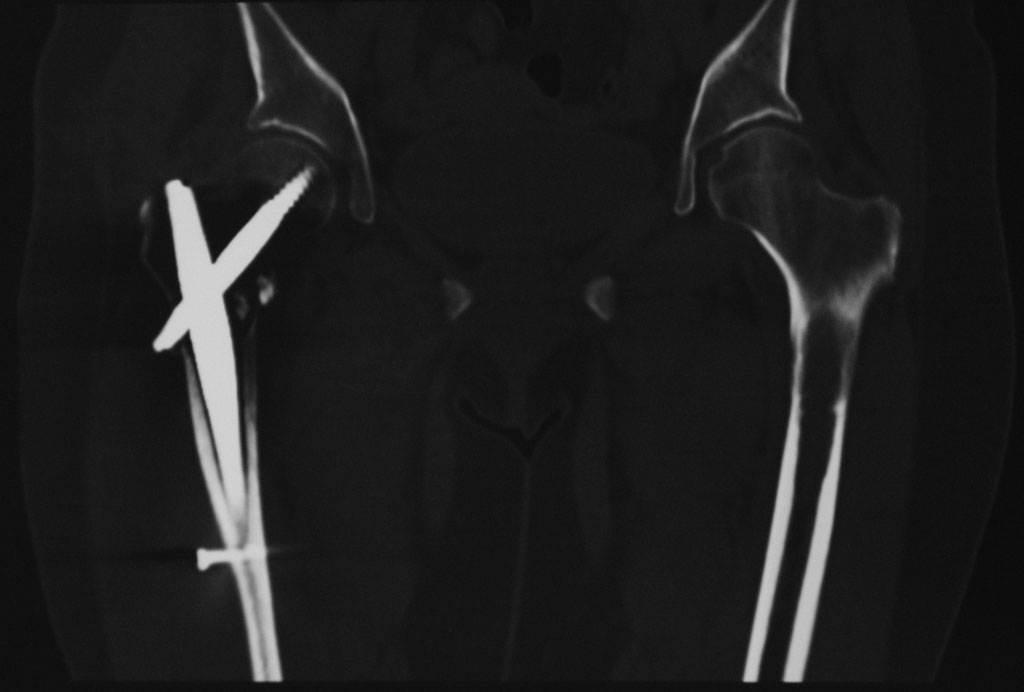

Киста проксимального метафиза бедренной кости

Добрый день. 2,5 месяца назад пациентке по поводу патологического чрезвертельного перелома правой бедренной кости (киста) был выполнена закрытая репозиция и БИОС гамма-гвоздем Stryker с заполнением полости Hydroset.

Гистологическое заключение: участки остеонекроза,хроническое воспаление. На этой неделе больная обратилась с жалобами на боли в области левого тазобедренного сустава. Со стороны оперированной ноги жалоб нет. Проведенное рентгенобследование выявило наличие полостного образования в проксимальном метадиафизе левой бедренной кости, перелом наружной стенки. Планируем выполнить БИОСлевой бедренной кости по методике аналогичной на правой ноге и этому случаю Какой фиксатор выбрать: длинную гамму или универсальный бедренный гвоздь?

Rg-грамма

Кликните для загрузки файла IMG_5485 copy_.jpg